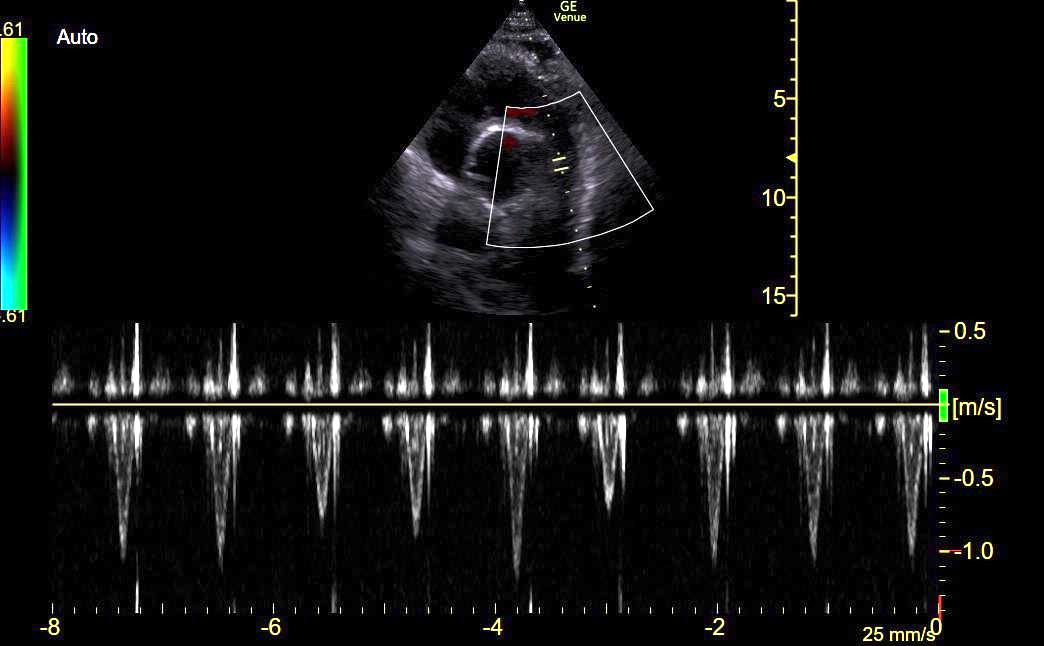

#POCUS ➡️large IVC (2.8 cm)